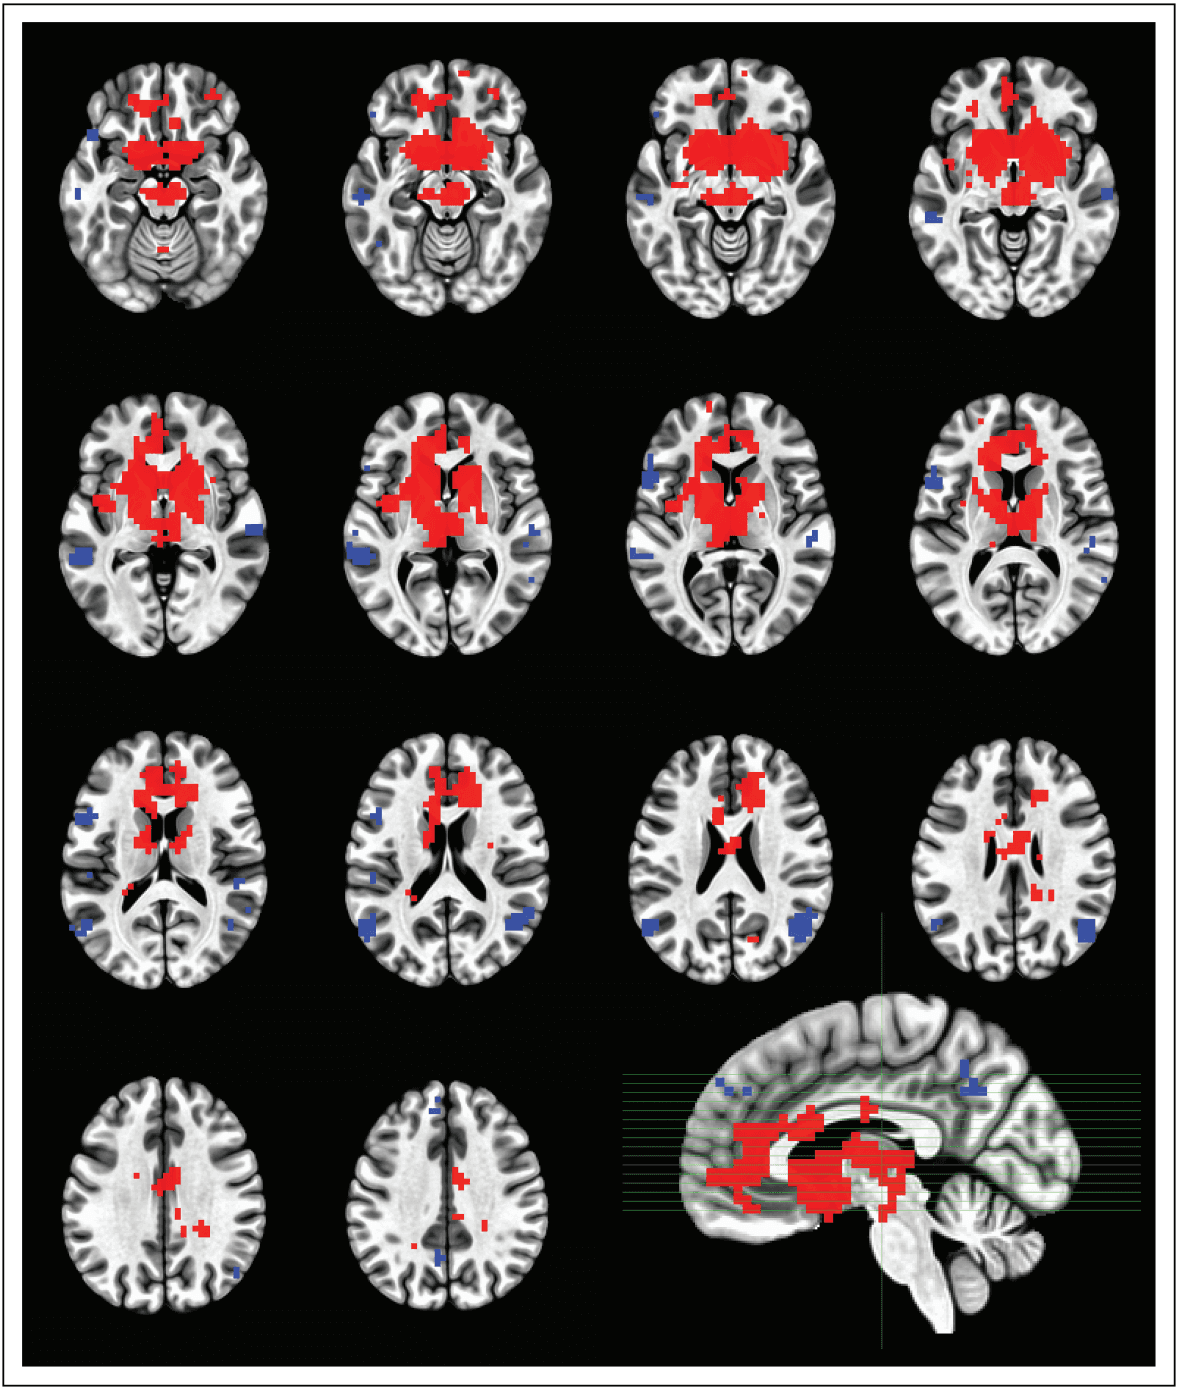

FIGURE 1.

Axial slices of prospective meta-analysis using neuroquery.org, indicating the predicted activations to the keywords ‘neuroimaging, substance use, addiction’. The colour codes represent threshold (at 3.0) z-values (positive ¼ red, negative ¼ blue).